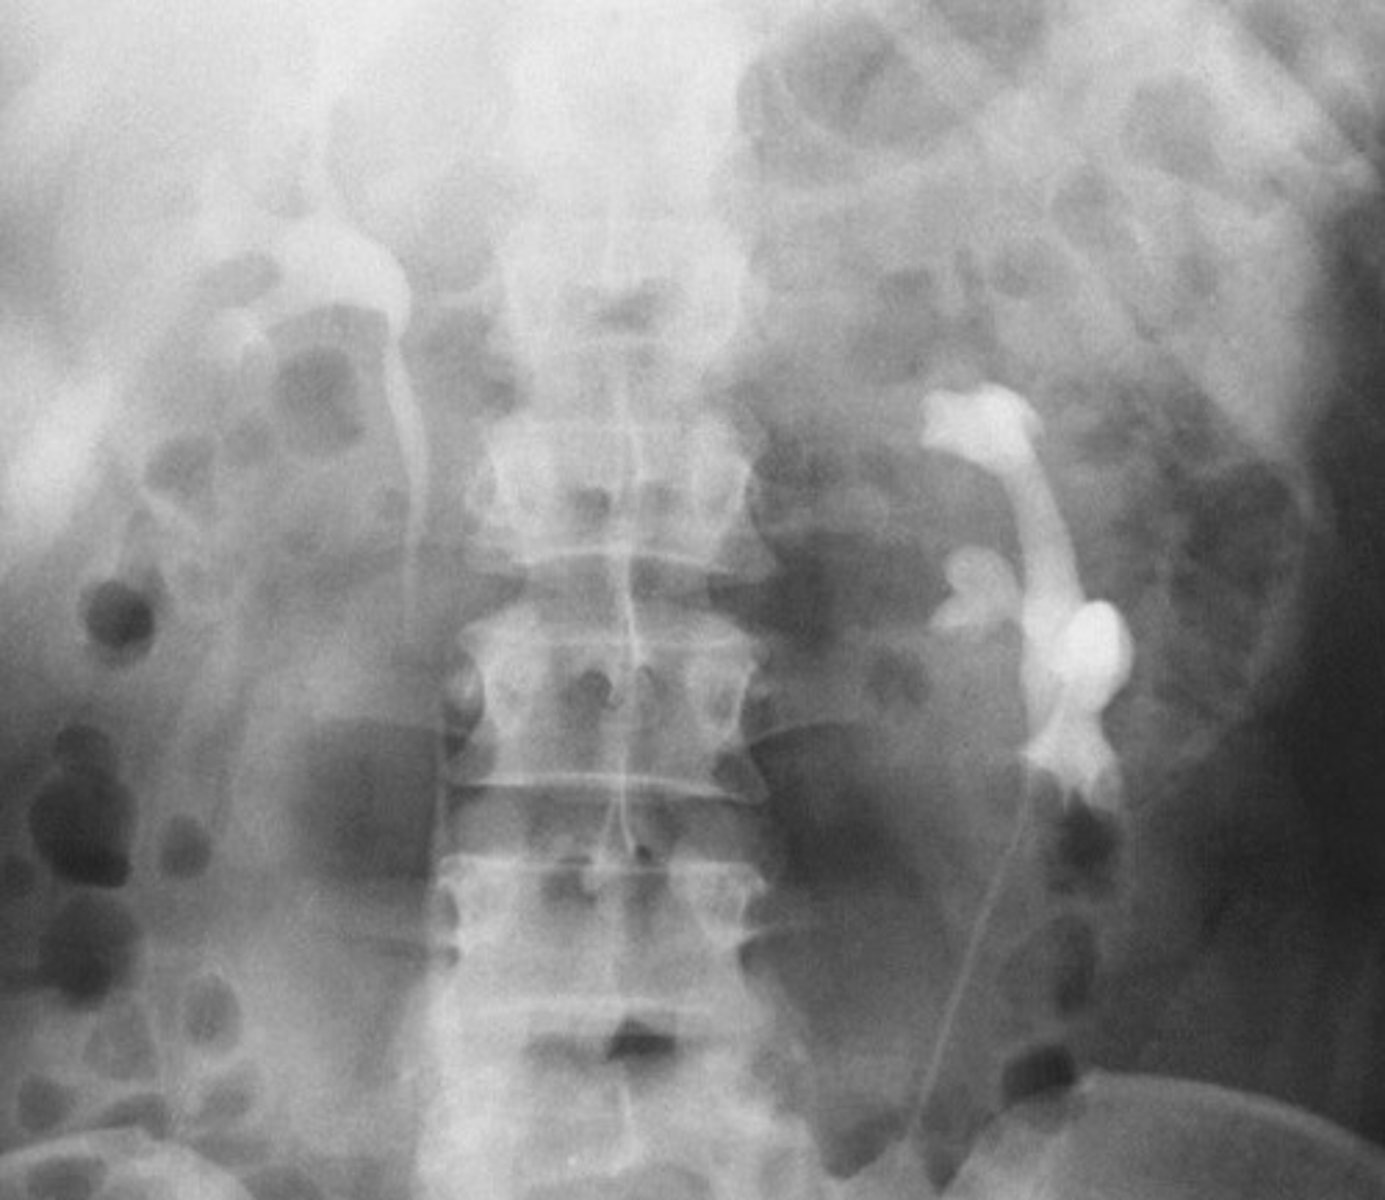

Bifid Kidney

What congenital anomaly occurs when the kidney has two renal pelvises and two ureters?

Duplication of Kidney

What congenital anomaly occurs when the entire kidney is duplicated?

- Pelvic Kidney

- What congenital anomaly refers to a type of ectopic kidney that is located in the pelvis and has a short ureter?

- When patients need a renal transplant, where are they placed?